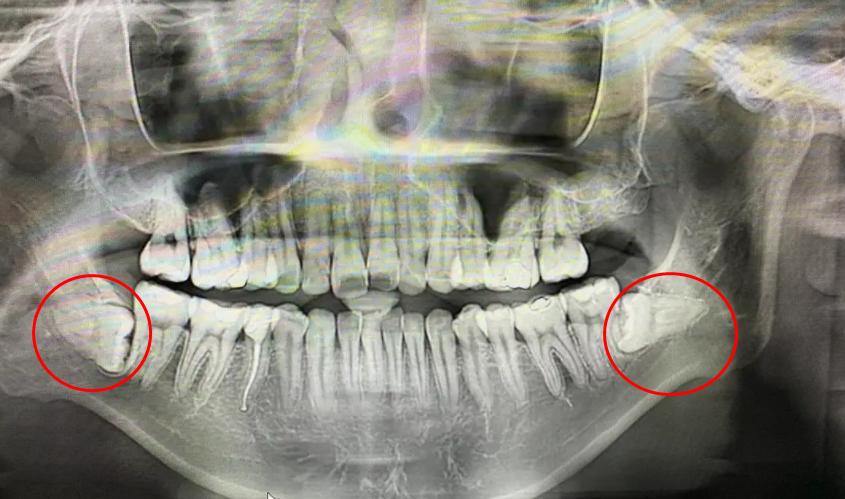

❷ 阻生智齿

智齿一般会在16-18岁左右开始萌出,它萌出的动力非常足,智齿的生长会推挤整个牙弓,特别是阻生智齿的危害,会挤压前面的邻牙,那么牙齿可能会出现越顶越歪、越顶越龅的情况。

建议:如果检查有阻生智齿,建议要及早拔除。